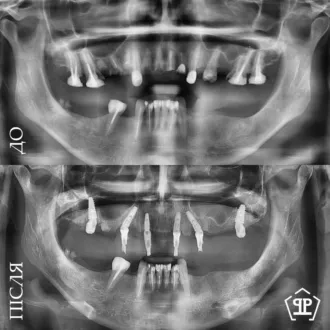

Показательный кейс одноэтапной имплантации All-on-6 на верхней челюсти. Импланты установлены в кости под углом, минуя гайморовые пазухи.

Выполнено тотальное протезирование на имплантатах по протоколу All-on-6 для обеих челюстей. На верхней челюсти установлена циркониевая керамическая конструкция на фрезерованной титановой балке, обеспечивающая высокую прочность и эстетику. На нижней челюсти изготовлена металлокерамическая ортопедическая конструкция на 6 имплантах. Произведено поднятие высоты прикуса, что позволило восстановить правильную окклюзию и гармонизировать профиль лица. Установлены несъемные конструкции, обеспечивающие полноценное функциональное и эстетическое обновление.